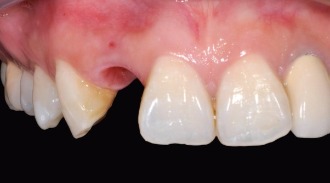

植牙前

植牙全瓷牙冠

植牙後